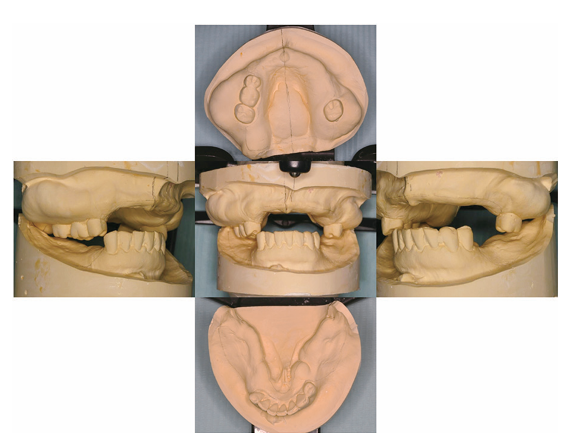

上顎残存歯はすべて抜去とし、十分なデンチャースペースを確保できるように研究用模型上でモデルサージャリーを行い、術後の口腔内を想定した。このモデルサージャリーを手術中の口腔内に再現できるように、アクリル製熱可塑性シートを用いてサージカルガイドを製作し、全身麻酔下において上顎抜歯術および骨隆起形成術を施行した。術後、創部の治癒が良好であることを確認し、上顎に全部床義歯、下顎に部分床義歯を装着した。その後、問題なく義歯を使用している。

<外骨症の石膏模型、咬合関係>

<術後の口腔内を予測したモデルサージェリー>